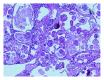

Hydatid cyst rupture into the abdomen is a serious complication of cystic hydatid disease of the liver (Cystic Echinococcosis) with an incidence of up to 16% in some series and can result in anaphylaxis or anaphylactoid reactions in up to 12.5% of cases. At presentation, 36-40% of hydatid cysts have ruptured or become secondarily infected. Rupture can be microscopic or macroscopic and can be fatal without surgery. Hydatid disease of the liver is primarily caused by the tapeworm Echinococcus granulosus and occurs worldwide, with incidence of up to 200 per 100,000 in endemic areas. Our case describes a 24-year-old Bulgarian woman presenting with epigastric pain and evidence of anaphylaxis. Abdominal CT demonstrated a ruptured hydatid cyst in the left lobe of the liver. A partial left lobe hepatectomy, cholecystectomy, and peritoneal washout was performed with good effect. She was treated for anaphylaxis and received antihelminthic treatment with Albendazole and Praziquantel. She made a good recovery following surgery and medical treatment and was well on follow-up. Intraperitoneal rupture with anaphylaxis is a rare occurrence, and there do not seem to be any reported cases from UK centres prior to this.